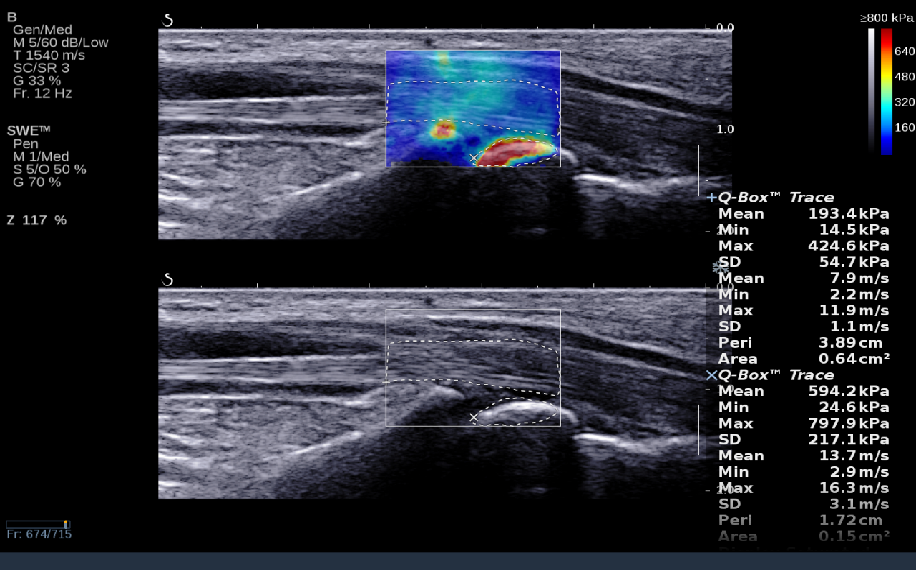

RTSWE实时剪切波弹性成像

?探头发射激励脉冲进行多点动态聚焦,利用马赫圆锥原理,形成大量的剪切波信号?颜色的变化与剪切波的速度相关,可直接体现肌肉肌腱等组织硬度值?实时、全幅、全定量

鉴别诊断、精准分级、定量评价、穿刺引导、疗效评估、随访观察